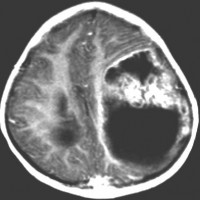

2歳の子どもの例

2歳の時に右の片麻痺と意識障害で発症しました。手術できれいにとれて,20年経ちますが再発はありませんし,運動麻痺もありません。この画像を見ると左の一次運動野が侵されていて,麻痺が治るということは信じられないのですが,2歳以下の小さな子どもの麻痺は治ることがあります。乳幼児のこの腫瘍は積極的な摘出を行った方がいいでしょう。